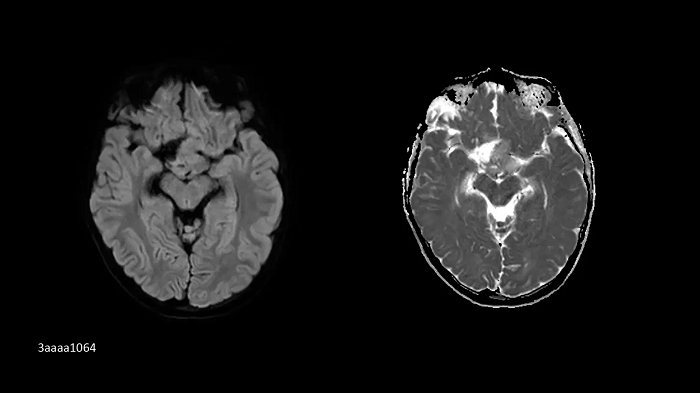

Neurology

SMS RESOLVE

Exceptional diagnostic performance with RESOLVE using high-resolution DWI and DTI of the brain, as well as increased efficiency with Simultaneous Multi-Slice (SMS).

PAT 2 SMS 2, b1000| 1.0 × 1.0 × 4.0 mm3 | TA 2:32 minutes

Image Credit: Customer contribution from Austria